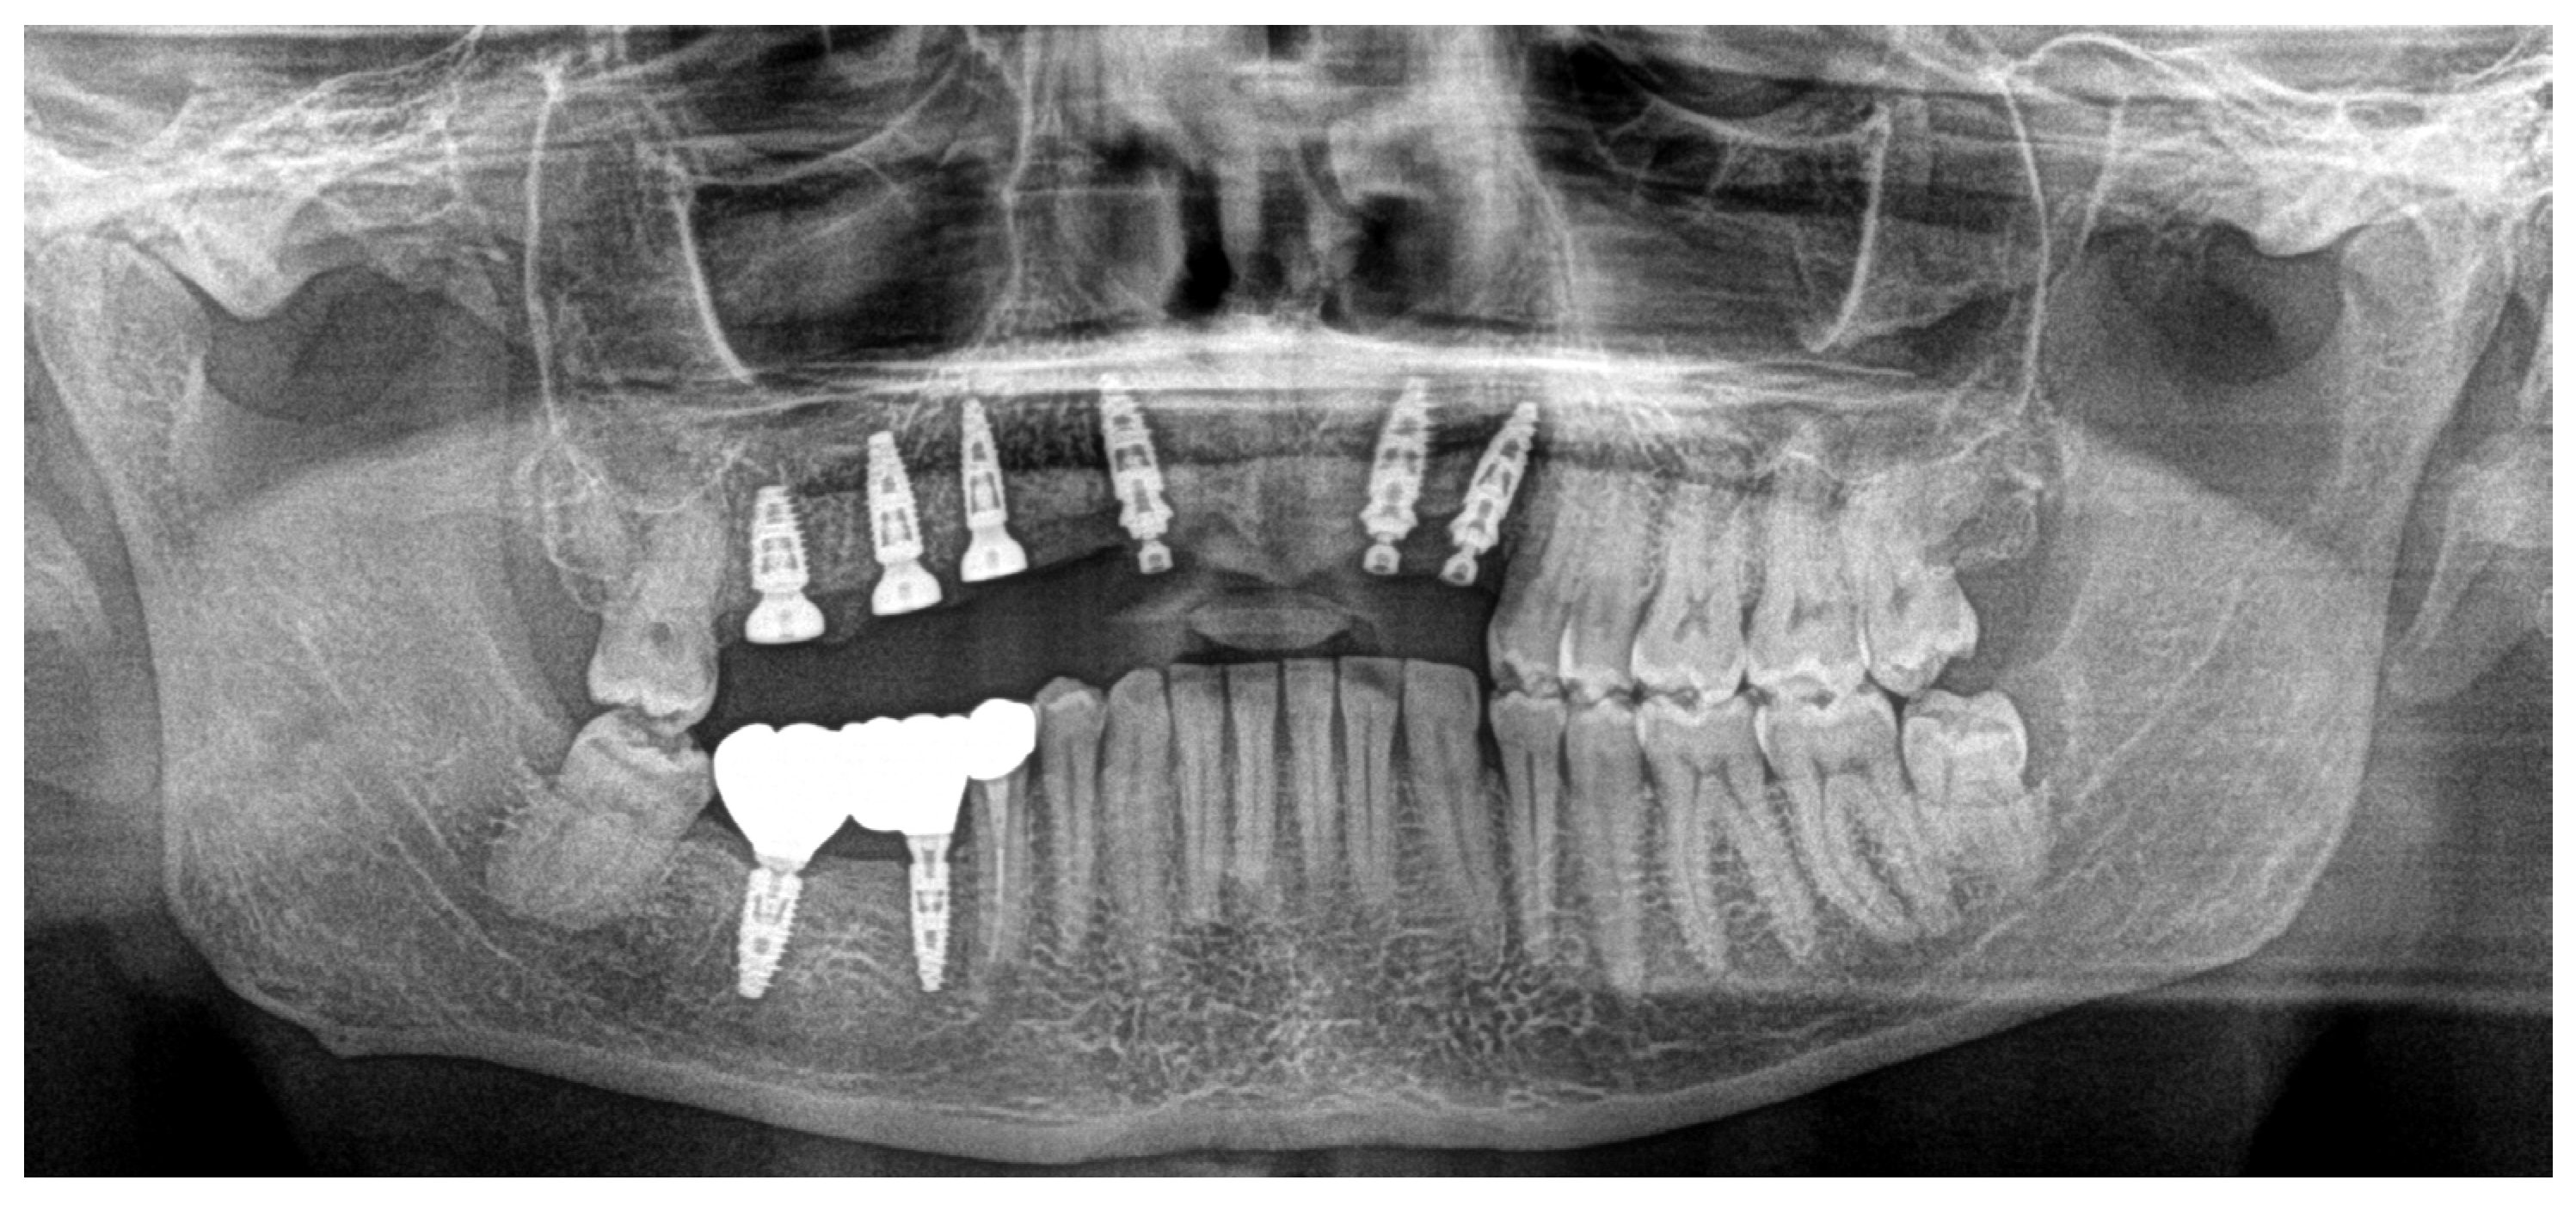

In June 2024, the implants were inserted in areas 16 and 17. Three months after the insertion of the last implants in 16-17 (4.2 × 10 mm and 4.2 × 8 mm, Biotech Dental, Allée de Craponne, Salon de Provence, France), it was possible to proceed with the digital impression-taking to proceed with a temporary prosthesis in PMMA (Figure 9) after a radiographic control (Figure 10).

Figure 10. OPT after all implant placements, in July 2024.